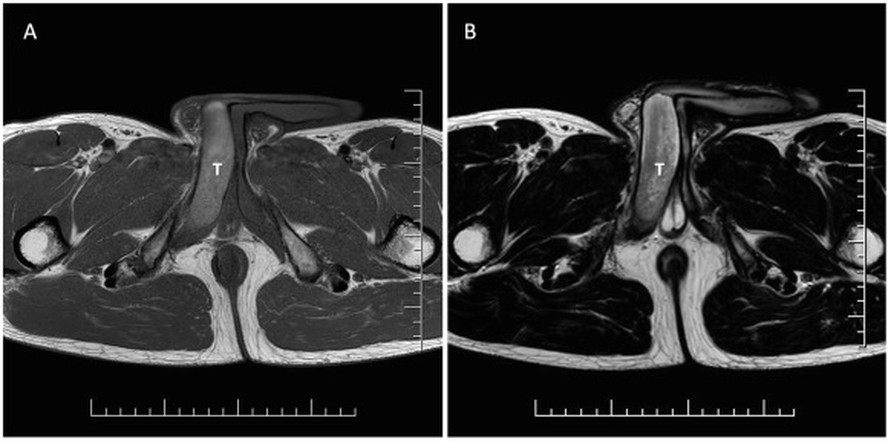

Depois de um treino de corrida, o eslovaco percebeu um caroço no pênis. Na mesma noite, ele começou a ter ereções dolorosas. Os exames mostraram um coágulo de 18 milímetros, e foi diagnosticado com uma trombose parcial nos corpos cavernosos do pênis (tecidos eréteis esponjosos que recebem sangue).

/i.s3.glbimg.com/v1/AUTH_1f551ea7087a47f39ead75f64041559a/internal_photos/bs/2023/v/N/IJzATrS3yw5huVdP7G4Q/1-s2.0-s2214442023003017-gr2.jpg)

Foto: Reprodução